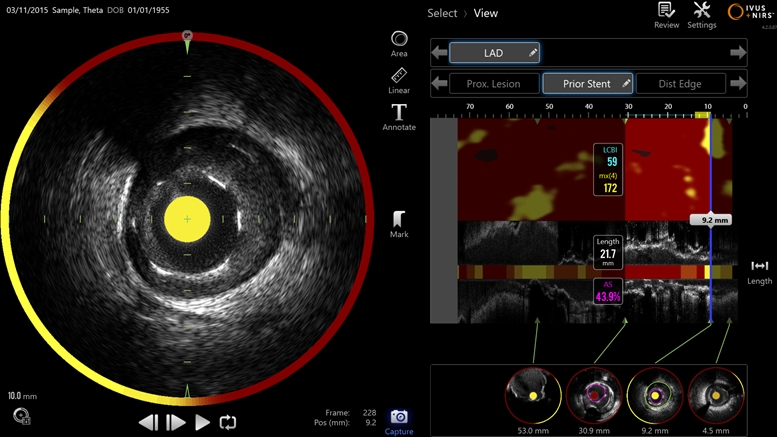

Massachusetts-based Infraredx, a subsidiary of the major Japanese medical equipment firm Nipro, has announced that its hybrid ultrasound/infrared (IVUS+NIRS) system for imaging blocked coronary arteries is now available in Japan.

The catheter-delivered imaging tool is said to exploit the dual modality approach by both mapping the shape of blocked blood vessels and identifying the chemical composition of the plaque creating the blockage. Japan's Pharmaceuticals and Medical Devices Agency (PMDA) approved the technology in August 2017.

The Makoto system features a "Dualpro" imaging catheter equipped with an extended ultrasound bandwidth. "By emitting and carefully processing a broad band of frequencies, the Dualpro IVUS provides best-in-class image resolution without compromising depth of field," states Infraredx, advantages said to translate to crisper arterial imagery.

That information is combined with near-infrared spectroscopic (NIRS) data and translated into a color-coded map to identify lipid core plaque (LCP) features. That information can help cardiologists distinguish between stable and dangerous plaques inside a patient's arteries.

"Coupled together, IVUS+NIRS arms cardiologists with unparalleled insights into the role LCP plays in heart disease," states Infraredx, referencing a number of clinical trials of the technology that underscore the importance of identifying LCP to predict and prevent serious heart attacks.